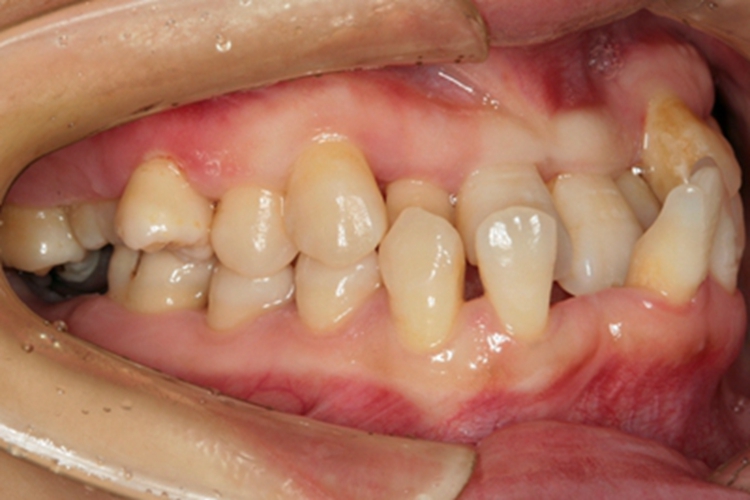

慢性牙周炎的损害可发生在牙齿,临床上可表现为患者出现牙齿松动,导致部分牙齿缺失,患者会有吐字不清楚、说话漏风的情况。

牙周支持组织发生慢性炎症,最终会导致牙周附着的组织发生炎症性慢性吸收和丧失,牙周支持组织消失以后牙齿就会缺失。